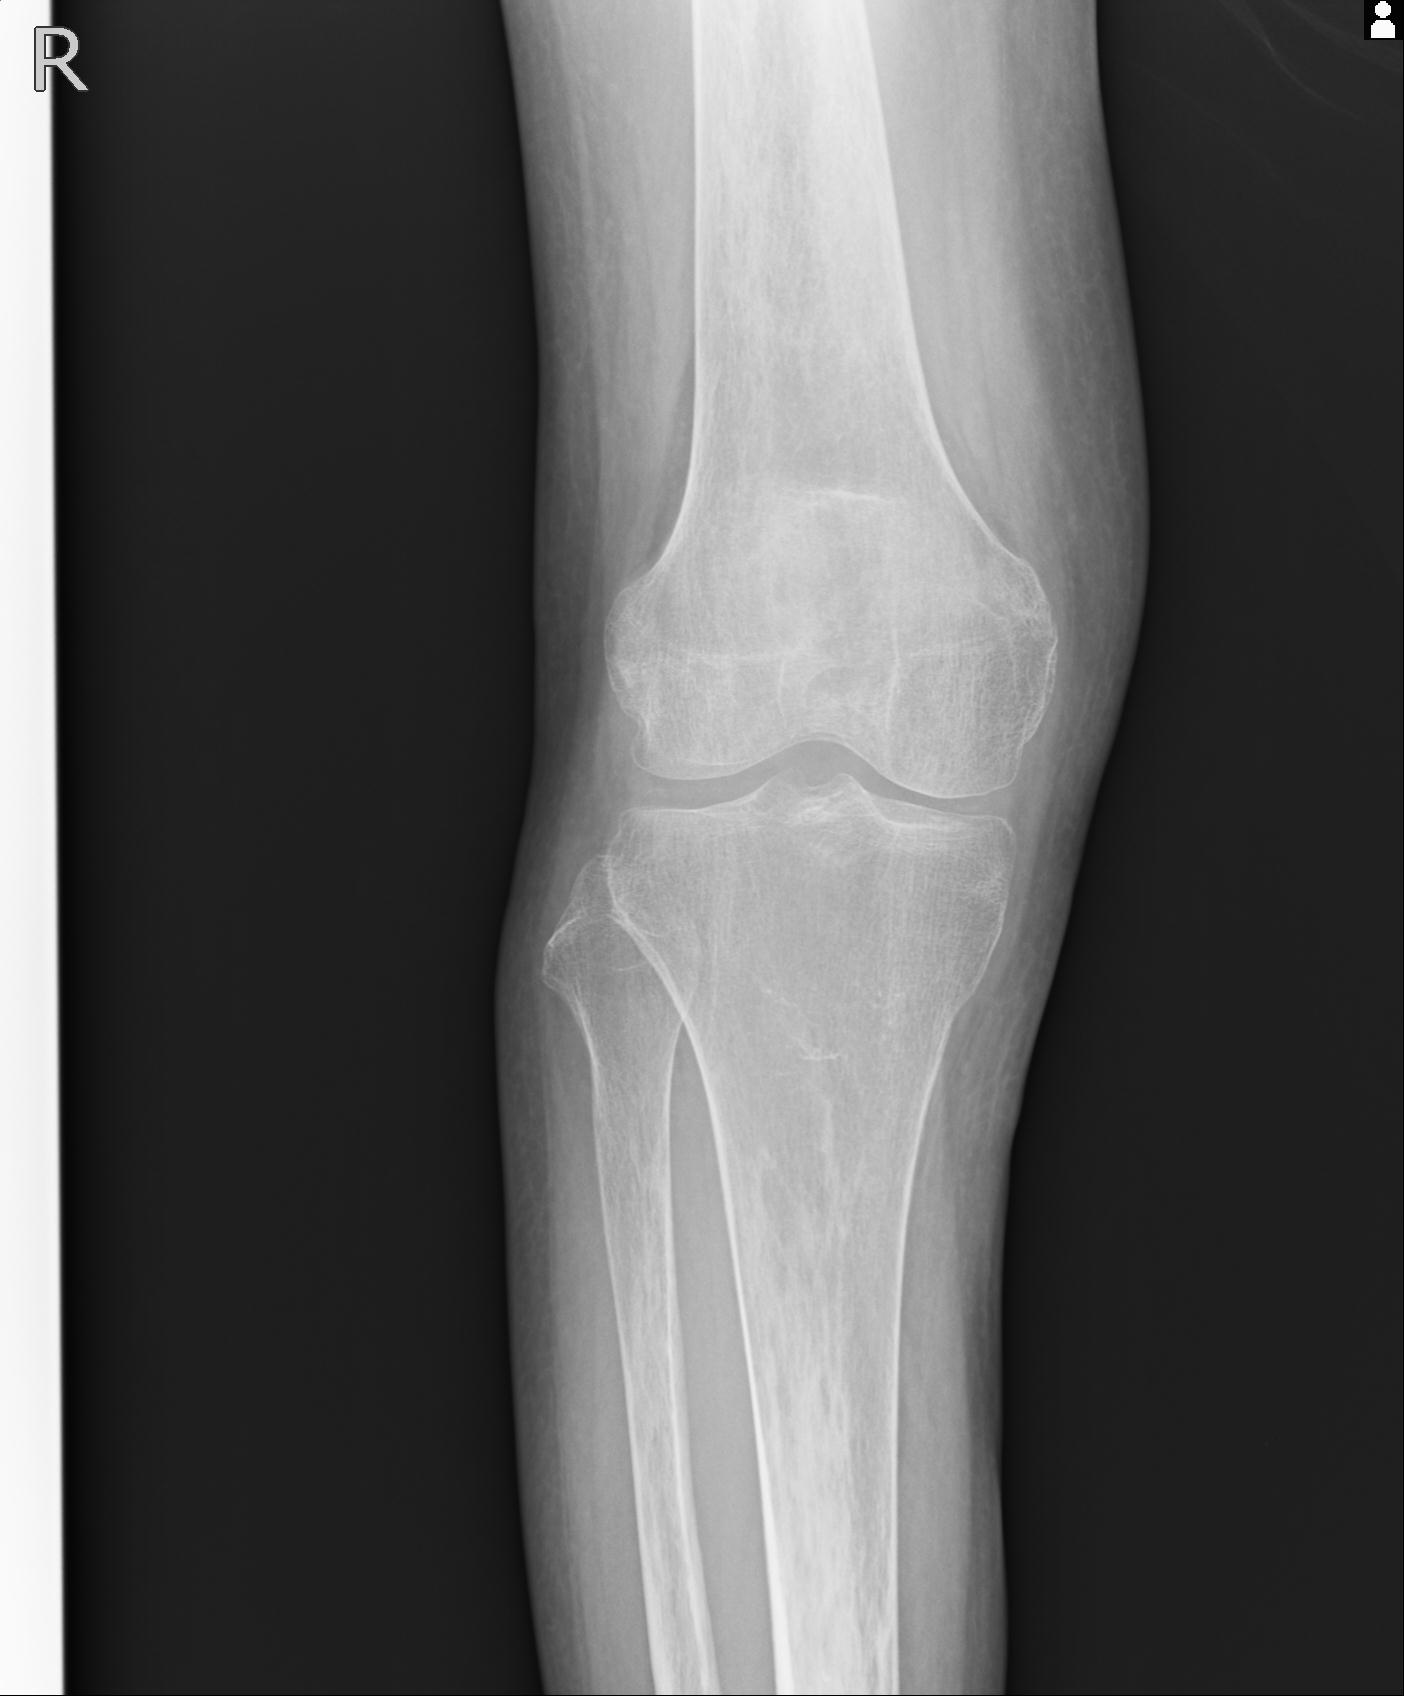

49554 3/13 膝 4R 3/16 4R 1/18 2R 78歳男性 膝蓋骨骨折